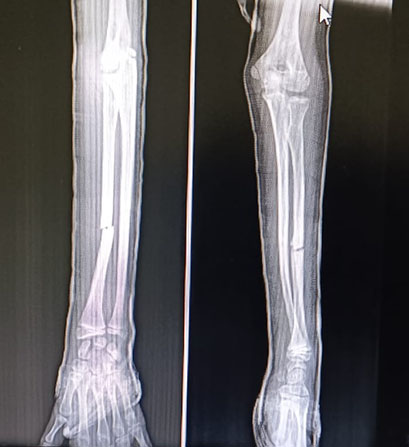

Vigilance and The Triumph of Remodeling

Conservative treatment requires exceptional vigilance to prevent loss of reduction. We conducted weekly X-rays for the first few weeks, the most critical period. The patient’s age allows for significant pediatric remodeling to finalize the correction over time.

The Outcome: A Full Functional Recovery

After six weeks, the cast was removed, and the patient’s recovery was swift and complete. He achieved perfect anatomical alignment and full range of motion (pronation/supination). He was spared the risks of surgery, anesthesia, and the need for future hardware removal.